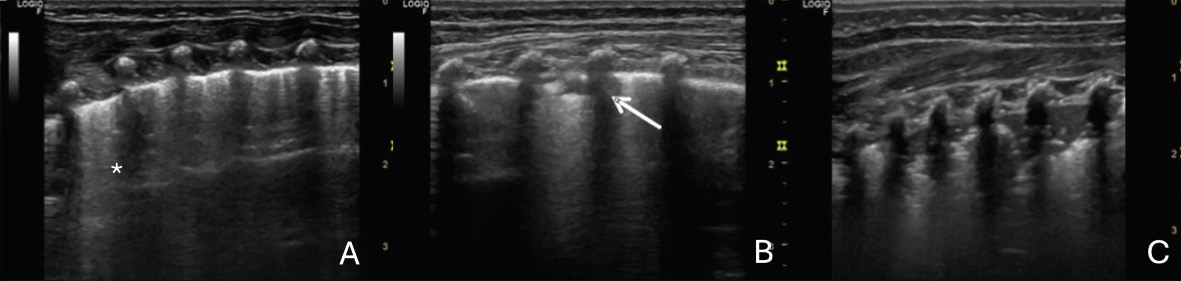

En el pulmón patológico, la alteración de la relación aire/líquido permite una mayor transmisión del ultrasonido, generando artefactos específicos o la visualización directa de estructuras, lo que define los diversos patrones ecográficos pulmonares(7) (Fig. 2).

Figura 2. Patrones ecográficos pulmonares: A. Patrón intersticial: aumento de tres o más líneas B (asterisco) por espacio intercostal, que borran líneas A. B. Patrón alveolo-intersticial: confluencia de líneas B, engrosamiento pleural y consolidaciones subpleurales < 5 mm (flecha). C. Patrón de neumonía: condensación > 5-10 mm, signo de desflecamiento o signo de la sierra en el borde inferior de la consolidación.